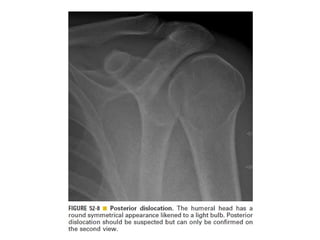

Skeletal trauma was presented by Dr Laith Fadhel with reference to Grainger's Diagnostic Radiology textbook. The presentation covered skeletal trauma as assessed through diagnostic radiology techniques. Key findings and treatments for skeletal injuries were likely discussed.